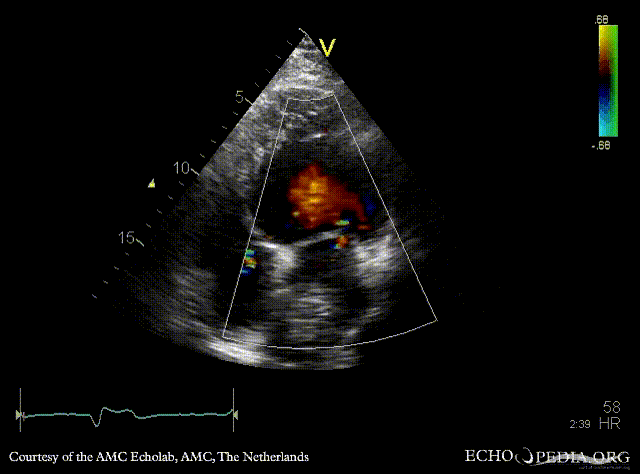

| Courtesy of: AMC Echolab, AMC, The Netherlands | |

| A3CH | A4CH with Color Doppler: moderate mitral regurgitation |